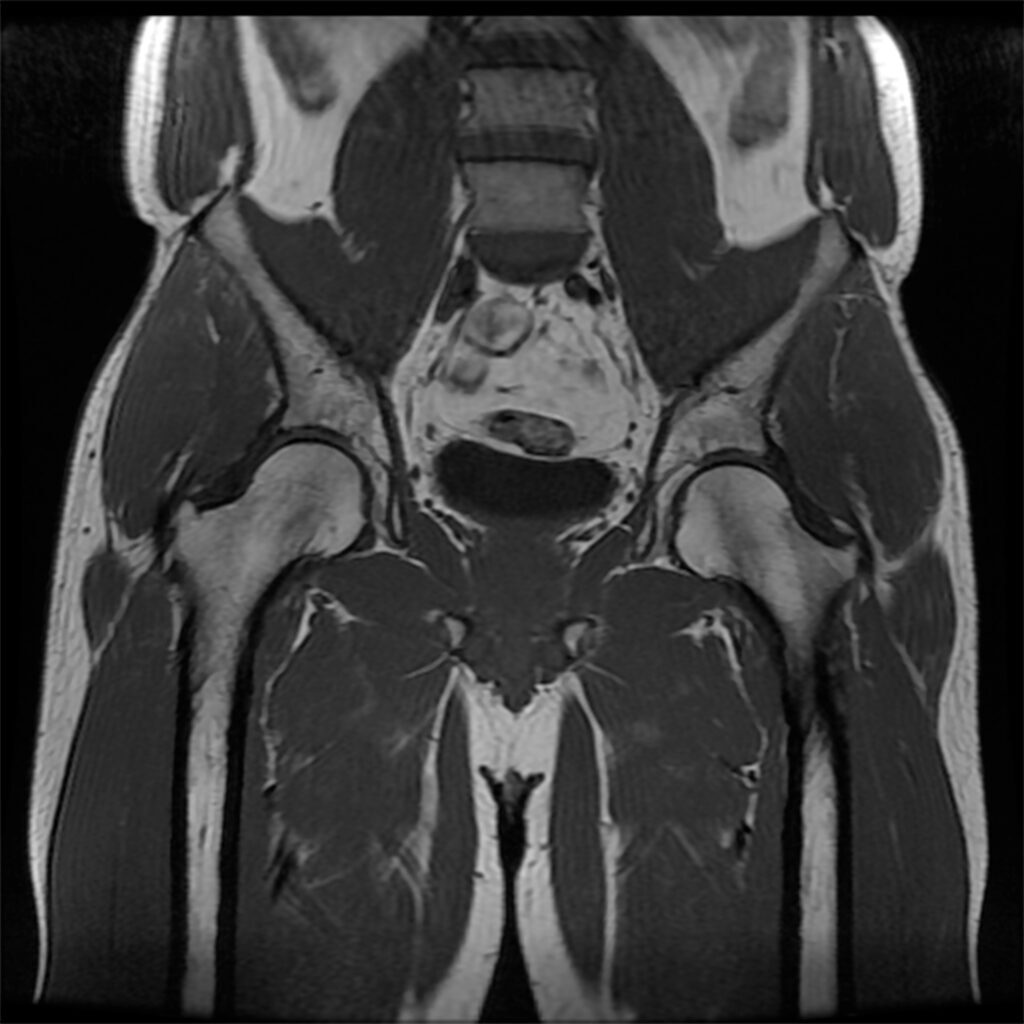

An August 2024 study(2) examined sacroiliac joint degeneration after lumbar or lumbosacral fusion surgery. In this study, researchers investigated whether multi-segment fusion or fusion-to-sacrum increases the risk of sacroiliac joint pathology, compared with single-segment fusion or a non-fused sacrum.

There was no significant difference in sacroiliac joint degeneration, as assessed by CT scan, between the two surgical groups: 14 (30%) and 19 (27%) patients in the single-segment and multi-segment fusion groups, respectively. Somewhat similar findings in non-fused sacrum compared to fusion-to-sacrum patients showed mild pain at one year and at two years, non-fused sacrum, mild pain, but, fusion-to-sacrum patients showed moderate approaching severe pain. CT scan revealed that 18 (26%) and 15 (31%) patients in the non-fused sacrum and fusion-to-sacrum groups, respectively.